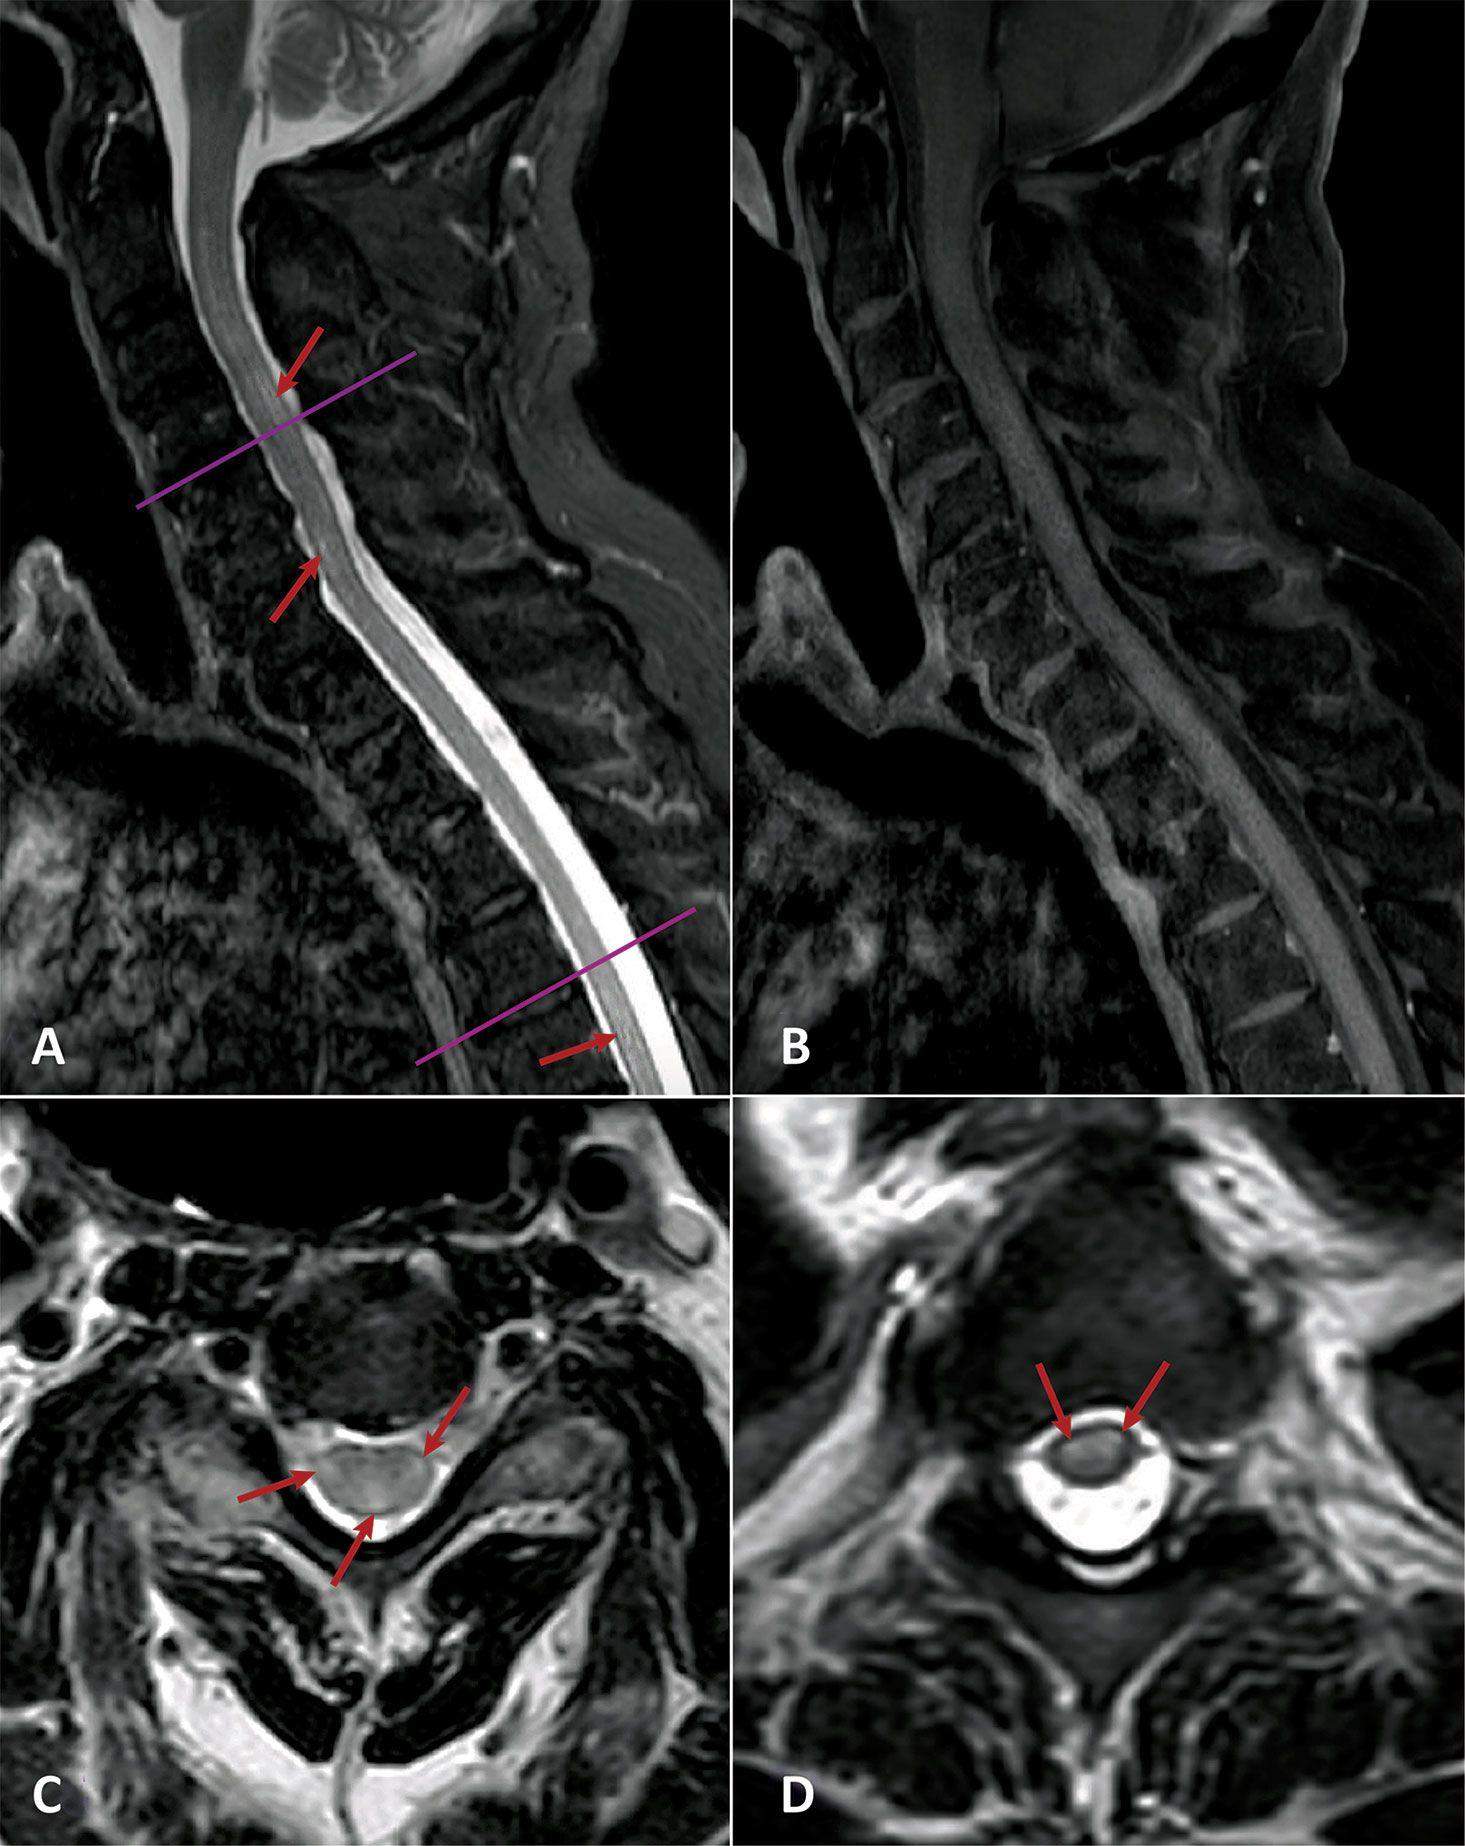

У всіх пацієнтів, розглянутих у дослідженні, був параліч і втрата чутливості, а медична візуалізація показувала наявність уражень спинного мозку.